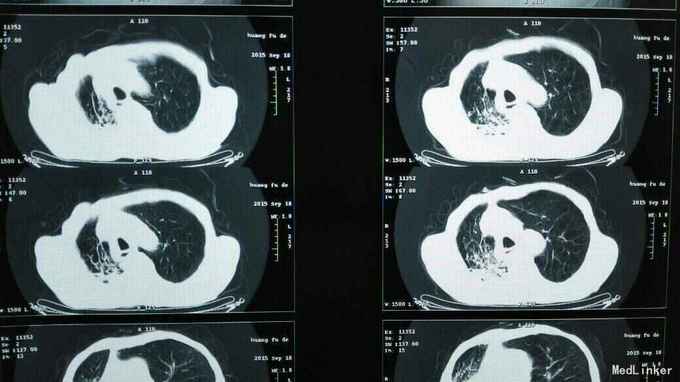

咳嗽,咳痰2年,加重伴发热2天 2年前始反复咳嗽,阵发性,白痰,量不多,无发热。无胸痛,咯血,未见消瘦。2天前受凉后咳嗽,黄痰,伴胸闷,气短,腰痛。监测体温39.0摄氏度。发热前无发冷寒战。

体温:39.0摄氏度,右肺下扣呈浊音,听诊呼吸音低;左肺扣呈轻音,听诊呼吸音粗,双肺少于湿性啰音。

肺癌骨转移 胸膜转移 阻塞性肺炎 建议支气管镜介入检查治疗,家属拒绝。 给予万古霉素抗感染治疗。